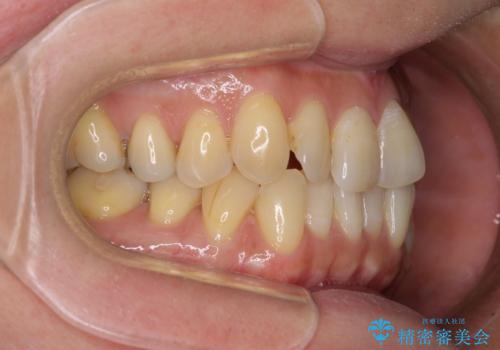

- 前歯のクロスバイトが気になり、インビザラインによる矯正治療を希望して来院された患者様です。

上顎側切歯(上の真ん中から2番目の歯)が舌側転位している場合、インビザラインでは仕上げきれないことが多く、更には無理して動かそうとすると歯髄壊死を起こすリスクが高いと言われています。

インビザラインで歯列を移動する前に、上顎前歯をワイヤー矯正で整え、その後上下歯列をインビザラインにて矯正治療を行うこととしました。

舌側転位している側切歯特有の、切縁の位置が不揃いであったり、根元が内側に引っ込んだ状態であったりという、インビザライン独特の仕上がりになることなく、きれいに整った歯列とすることができました。